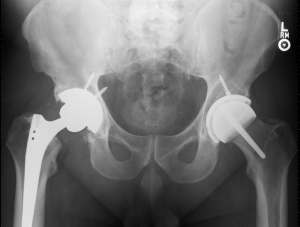

With correct insertion tools, shell insertion and intraoperative liner engagement have been proven safe. Long-term studies including retrieval data have shown that thin components are successful (22,24). It is possible to under-ream the acetabular component by 3 mm and still be able to insert and assemble the two-piece prosthesis intraoperatively. With under-reaming, critical acetabular bone is preserved. Because under-reaming is possible, most patients can be treated with the same size polyethylene acetabular component or just a 2-mm incremental increase compared to total hip replacement (26,32) (Figure 2).

The follow-up period ranged from 5 to 21 years (median, 9.5 years). Patient demographics are shown in Table 1. The postoperative functional results all improved significantly (Table 2). Eighty percent of the patients achieved a postoperative UCLA score of 8 or greater. The average acetabular component inclination was 41° (range 30° to 53°) and the average anteversion was 15° (range, 0° to 25°). The average femoral anteversion was 13° (range, 0° to 20°). All femoral components were neutral or placed in a valgus orientation with respect to the native femur. Screw fixation was used in 9% of patients when the shell was ≥20% uncovered.